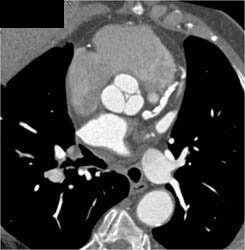

Diagnosis

Diseased LAD